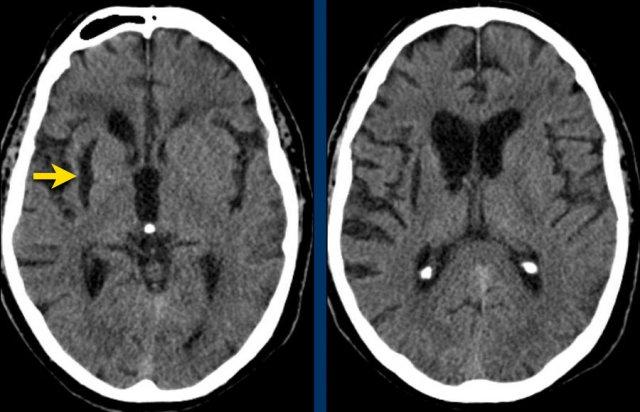

Đồi thị

Xuất huyết tại đồi thị thường gặp trong tăng huyết áp.

Bệnh nhân này nhập viện với não úng thủy do xuất huyết não thất (hình bên trái).

Lưu ý vùng tăng tỷ trọng rất nhỏ tại đồi thị trái, là điểm khởi phát của xuất huyết.

Theo dõi một ngày sau (hình bên phải).

Bệnh nhân được phẫu thuật đặt dẫn lưu não thất để điều trị não úng thủy.

Lưu ý đồi thị bên trái giảm tỷ trọng với ổ tăng tỷ trọng dai dẳng ở vị trí trong.